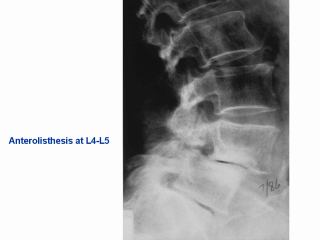

This radiograph shows you

anterolisthesis at L4-L5. This didn’t reproduce very well but this is L4 and this is L5

and you can see that this one has slipped anteriorly relative to L5. This is a fairly

large slip. Actually in some of the experiments, some of the work that we’ve done, this

is basically what we measure, the extent of the slippage. When this happens, what this

does is called encroachment upon the spinal canal making it narrower in this area so then

you are more likely to get pinching of the spinal nerves. |